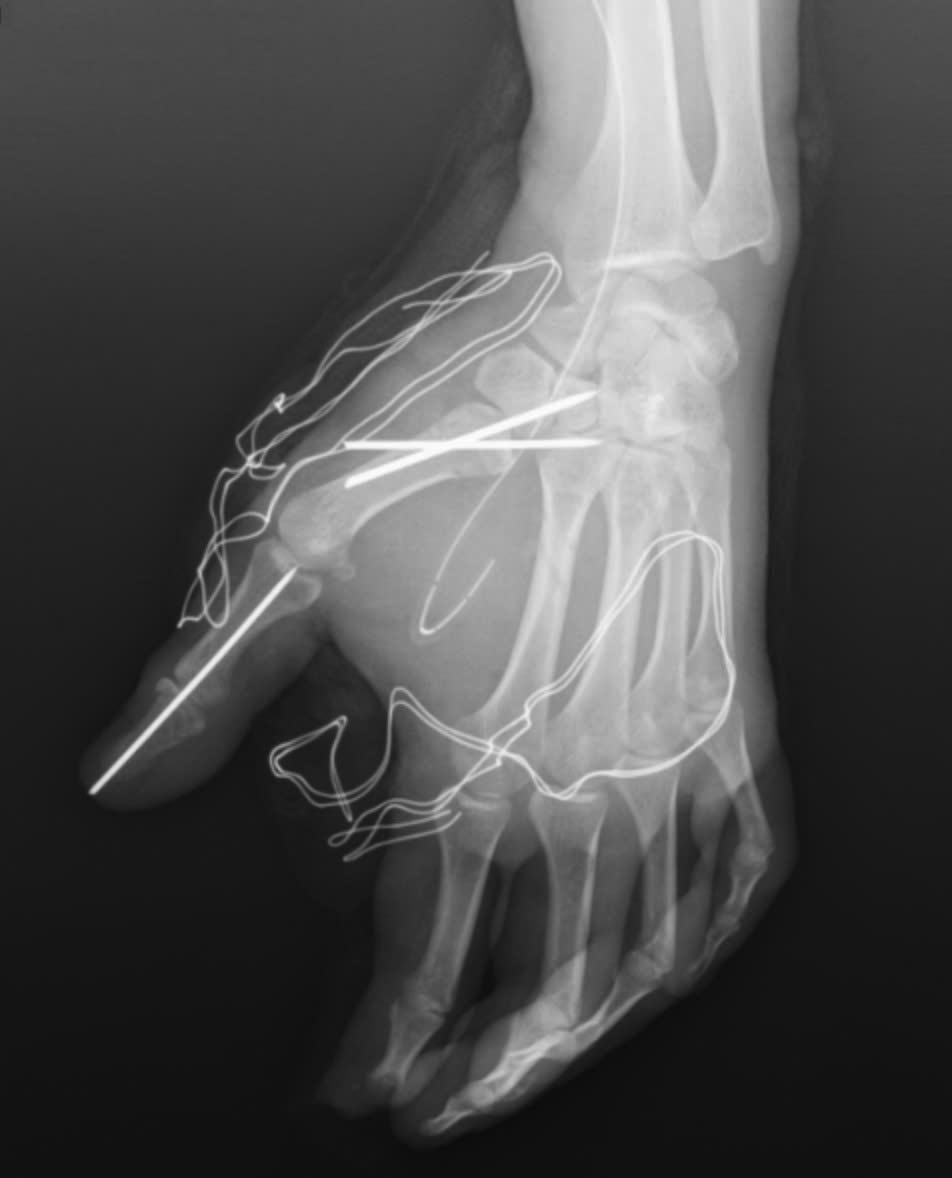

Bàn tay nạn nhân bị dập nát sau tai nạn pháo nổ.

Trong quá trình phẫu thuật, các bác sĩ khoa Phẫu thuật Chấn thương Chỉnh hình và Y học thể thao đã tiến hành cắt lọc tổ chức dập nát, lấy bỏ dị vật trên bàn tay của người bệnh. Đồng thời, vết thương được làm sạch, các cấu trúc gân, thần kinh và mạch máu còn lại được bảo tồn tối đa. Cuối cùng, các bác sĩ cố định xương gãy và khớp bị trật cho người bệnh.